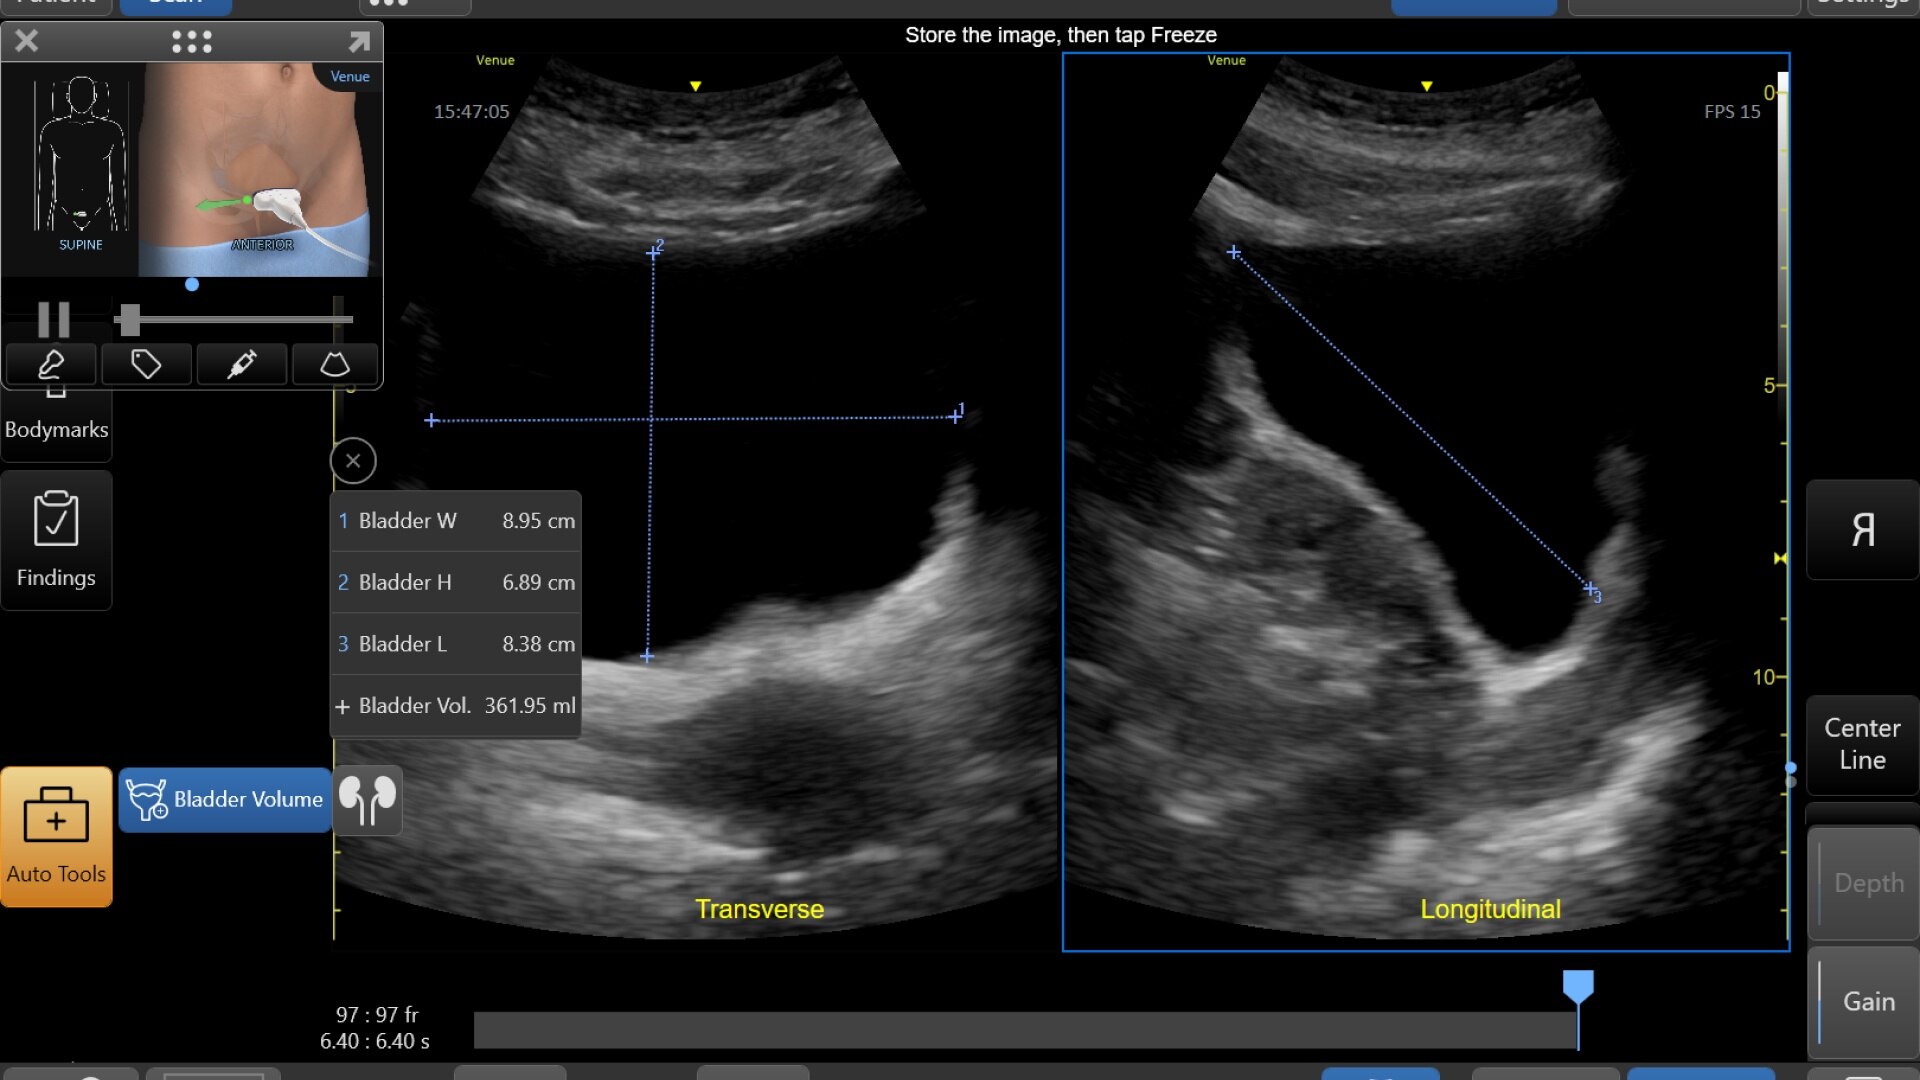

Quickly assess kidneys and the bladder with Renal Diagram

Simplify documentation and provide easy follow up for patients with suspected hydronephrosis. No need to type findings; simply assign a label from a pre-populated list that correlates with images.

renal-diagram-review-desktop